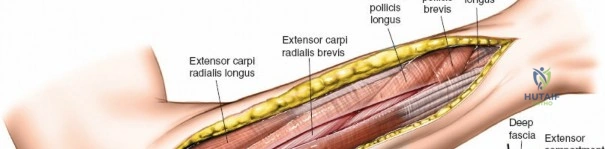

Release of Dorsal Compartment: Identify the investing fascia over the extensor muscle group (ECU, EDM, EDC, supinator). This fascia is incised longitudinally throughout the length of the incision. Ensure full decompression of all muscle bellies.

- Proximal Consideration: The supinator tunnel, through which the posterior interosseous nerve (PIN) passes, should be carefully inspected and released if necessary, though it is less commonly a primary compression site in acute compartment syndrome.

The dorsal fascia is incised here, allowing the extensor muscles to expand. The extensor digitorum communis and other dorsal muscles are visible.

- Proximal Consideration: The supinator tunnel, through which the posterior interosseous nerve (PIN) passes, should be carefully inspected and released if necessary, though it is less commonly a primary compression site in acute compartment syndrome.

Release of Mobile Wad (Lateral) Compartment: This compartment contains the brachioradialis, ECRL, and ECRB. The fascia overlying these muscles should also be released through the dorsal incision, often by extending the fascial release more radially. The superficial radial nerve runs deep to the brachioradialis in its distal third; care must be taken to avoid injury during distal extension of the fascial release.

This image illustrates the release of the mobile wad, specifically showing the decompression of the brachioradialis. The full extent of the fascial release should be visualized.